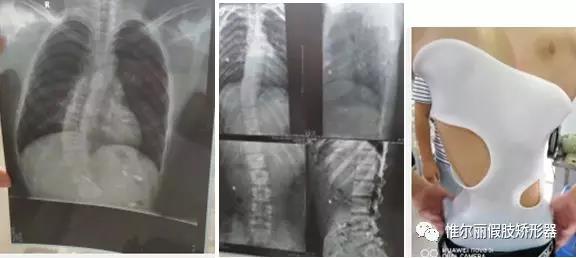

前不久,貴公司遇到過一個28歲的男生(如圖),已參加工作,出現些不正常癥狀,想要矯正,但時間已經來不及了。只能控制不往更壞的地方發(fā)展。

小湯側彎的度數還是比較厲害的,Cobb角已經接近30多度°及旋轉的。就醫(yī)后,醫(yī)師建議手術,但家長咨詢惟爾麗張教授后通過支具診治。

張教授為小湯制定了診治策略,運用他專門指導技術及佩戴支具,從而達到明顯矯正脊柱的效果。

通過X光片我們可以看出,患者的側彎角度明顯改觀,脫離了手術指征。所以,對于大度數脊柱側彎還是有機會的。但是與孩子堅持是密不可分的。